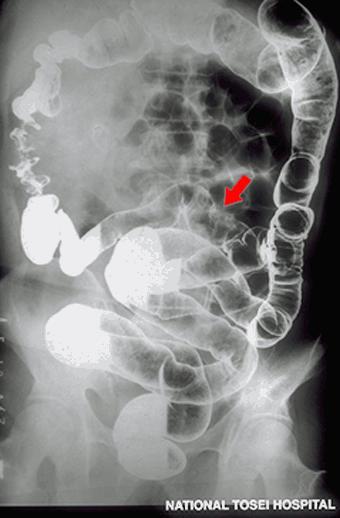

Type 0-IIa+IIc (superficial elevated and superficial depressed type) early ileal carcinoma demonstrating submucosal invasion (sm) diagnosed preoperatively (presented by Dr. Y. Ozeki.)

Malignant epithelial tumor/Adenocarcinoma

Small intestine/Jejunum

X-ray

Type 0/IIa (IIa+IIc) Superficial elevated and depressed type

25 - 29

submucosa